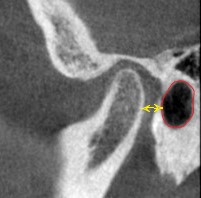

この状態になった時のこの患者さんのCTスキャンの比較はこちらです。

治療前 左側

治療後 左側

治療前 右側

治療後 右側

関節圧迫が取れているのがわかるでしょうか?

これが治療後の状態です。

赤い線は耳の穴です。

顎関節は耳の穴の裏側に位置します。

耳の穴を関節が圧迫していたらどうなりますか?

耳鳴り、難聴、めまい、統合失調症

耳にかかわる病気はこれが理由かもしれません。